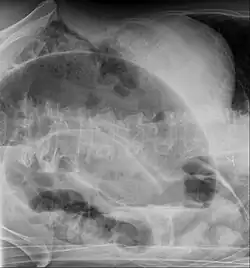

Coronal CT of the abdomen, demonstrating a volvulus as indicated by twisting of the bowel stock